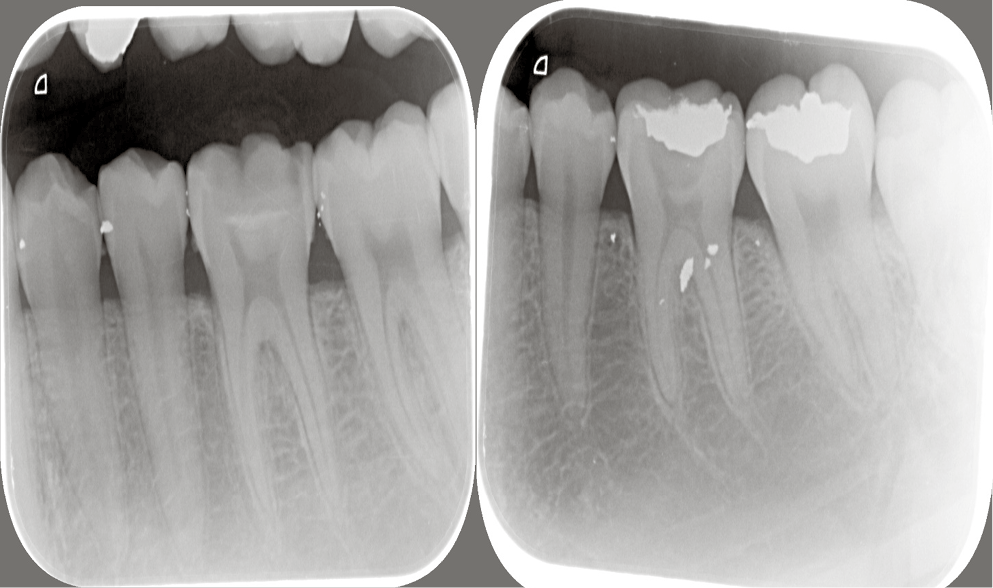

Pre-operative radiographs were taken using a digital X-ray machine (Kodak 2200; Kodak, Rochester, USA) with an imaging plate (digital sensor size 2; Dürr Dental, Bietigheim-Bissingen, Germany). Local anesthesia (Mepecaine- L) was administered with the infiltration technique and the nerve block technique for upper and lower arches respectively. Heavy sheet rubber dam isolation was applied, and class I cavities were prepared. Selective caries excavation technique was used to clean the pulpal floor using a spoon double ended excavator until leathery or firm dentin was reached as shown in Figure 2.

Assessment of remineralization

To assess the dentin remineralization, a digital X-ray machine (Kodak 2200) was used with DBSWin software at baseline, 6 weeks and 12 weeks, using a size 2 digital sensor and posterior parallel kit for image standardization that has 2 ends: one for X-ray cones and the other for the sensor. Then, the sensor was removed and scanning was performed with the use of Dürr Dental Vista Scan. The scans were stored for analysis.

Measurements in each sample were fixed for all samples at assessment intervals; 2 lines were drawn, one along the cementoenamel junction (CEJ) for reference and a second line parallel to it at the bottom of the cavity. The distance between the 2 lines was standardized for each tooth and measured by a vertical line connecting them. The DBSWin software was then used to determine the length in pixels and fix it for each sample. Three points on this line (at its start, middle, and end) were determined. The intensity of these points was recorded at each follow-up visit.

The pixel grey measurement in digitized radiograph method was used to assess remineralization. A study by Mittal et al. reported that the average pixel grey value can be used to quantitatively monitor caries remineralization, this is based on remineralization being a slower process than demineralization.26